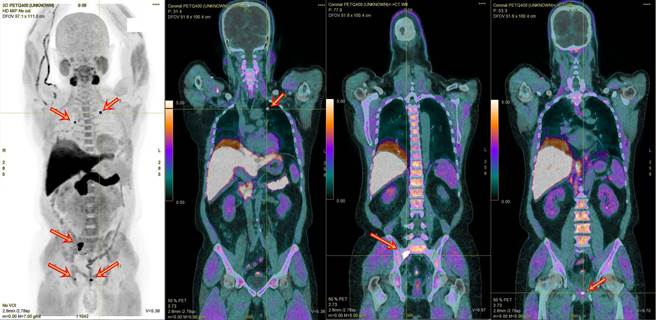

奥摄敏全身正子影像检查,精准找出48岁患者摄护腺肿瘤与转移至肺与骨之肿瘤,各种不同角度之检查影像,红箭头为肿瘤处。(梧栖童医院提供)

另外还有一位48岁吴姓患者,一年多前曾因摄护腺癌接受过手术,术后定期回诊检查,去年进行PSA筛检时发现指数高达160(40~49岁正常值应为2.5ng/ml以下),欧宴泉副院长诊视后建议进行奥摄敏全身正子影像检查,精确发现除摄护腺长出肿瘤外,肿瘤还转移到了肺、骨,立即安排进行放射治疗,目前由放射肿瘤科叶启源主任进行真光刀放射治疗中。